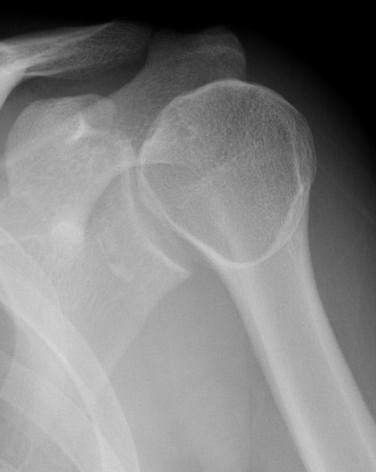

AP Xray

Abnormal overlap of humeral head on glenoid

Light-bulb sign - globular head secondary to internal rotation of the humeral head

Vacant Glenoid Cavity - > 6 mm space between humeral head and anterior rim of glenoid

Normal scapular lateral